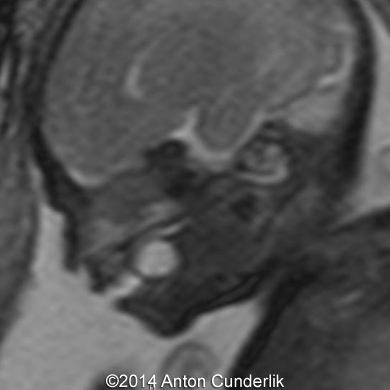

Our examination revealed a cystic, biloculate structure within fetal tongue. MRI imaging confirmed the finding. The newborn was delivered at term via cesarean section (male, 3210 g, 50 cm, Apgar score 10/10).

Image 8, 9, 10: 33 weeks of gestation; MRI images showing the cystic structure within the fetal tongue representing thyroglossal cyst.